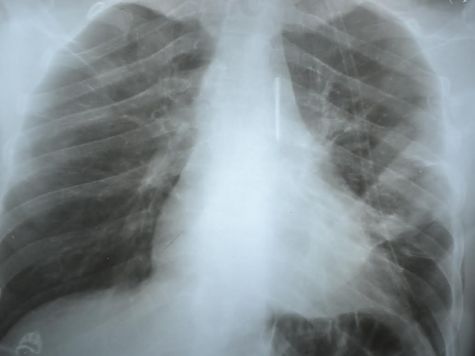

- Ну, вы знаете, что кассетный боеприпас начинён большим количеством поражающих элементов. То, что мы доставали из тел, выглядело как иголка с оперением. Такая себе железная стрелка. У меня есть фотографии этой стрелки, когда она извлечена и есть рентгеновский снимок подобной стрелы, которая застряла возле лёгочной артерии.

- Да. Это был ополченец из-под Славянска. И родом он,кстати, был из Славянска. Подобная стрела попала ему в яремную вырезку, проще говоря, чуть пониже шеи. И прошла в лёгочную артерию. Это магистральный сосуд, который отходит от сердца. Там эта стрелка инкапсулировалась – то есть возникло вокруг неё воспаление, и этот воспалительный инфильтрат держал её, как в капсуле. И он с этой стрелой ходил несколько месяцев пока не попал в нашу больницу. Мы сделали снимки, всё это обнаружили и, поскольку доставать оттуда такую вещь было очень опасно- можно получить кровотечение с совершенно непредсказуемым исходом, то была выполнена операция с применением методики искусственного кровообращения, и этот боеприпас мы всё-таки извлекли.